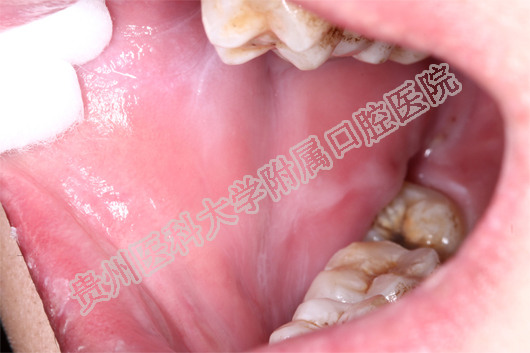

(患者治疗前后的口腔黏膜病损对比 上图:治疗前 下图:治疗1周后)

当天值班的王珣主治医师为小邓这一特殊病人加号,并作了相关检查后诊断小邓为药物引起的“过敏性口炎”。王珣医师介绍:小邓来的时候已经很严重了,上下唇、手背、拇指已经出现红色斑块,并且全口黏膜溃烂、生殖器可见不规则糜烂面。像小邓这种情况根本无法进食、而且疼痛难忍。若不及时救治,很有可能造成电解质紊乱。随后王珣医生询问病史发现:原来,5天前,小邓因智齿冠周炎自行服用了“消炎片”,随后出现全口黏膜溃烂,无法进食而且说话都困难,随后皮肤上也起红斑,生殖器也开始溃烂,疼痛难耐,无法入睡,人也明显消瘦了许多。

王珣医师嘱患者停用可疑药物,并为他对症用药。由于“过敏性口炎”的病情发展变化较大,王珣医生还为患者留了自己的微信,以便实时了解小邓的病情变化。1周后,小邓复诊时口腔生殖器黏膜已经痊愈,上下唇及手背、拇指的斑块也基本消退。小邓非常感谢williamhill官网附属口腔医院,在疫情的特殊时期能为他开通绿色通道,让他的疾病痊愈 。